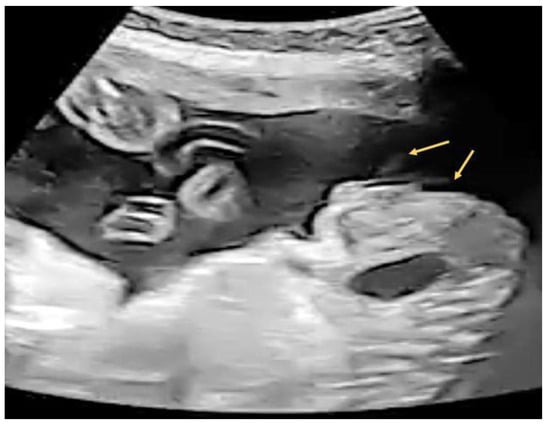

2.3. Case 3